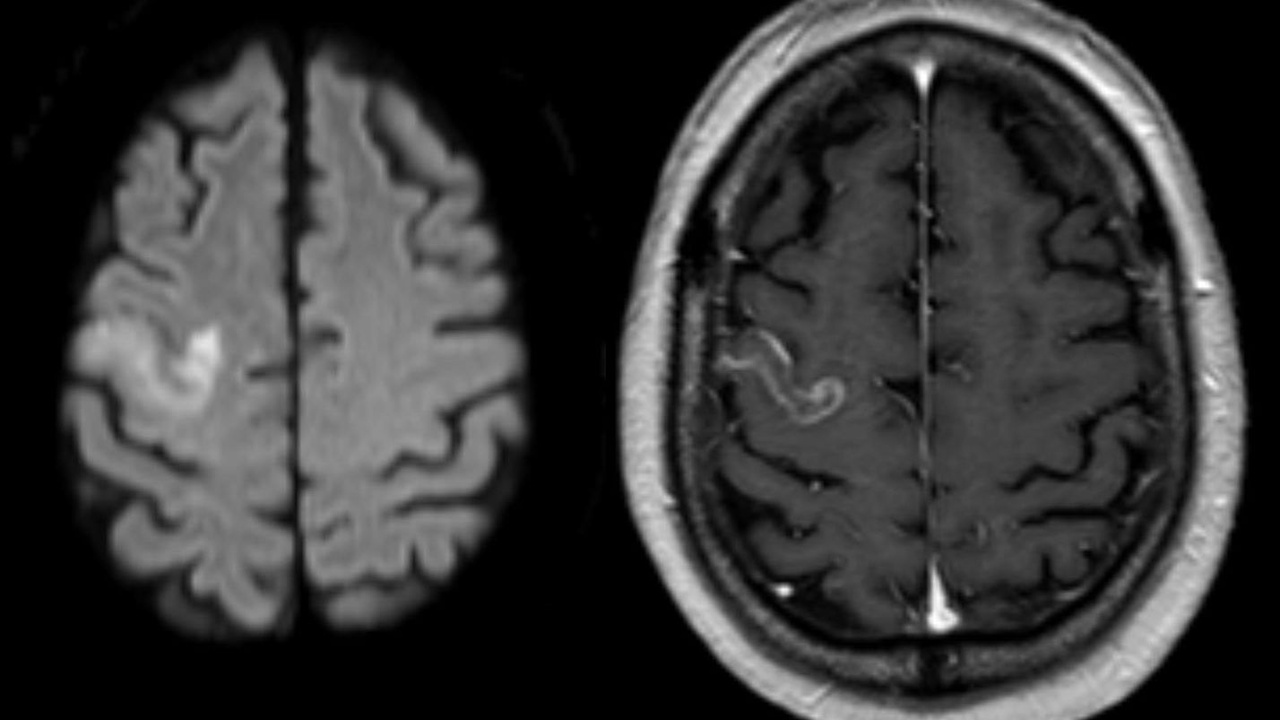

The single most familiar use of gadolinium is as the active center in MRI contrast agents. Gadolinium ions (Gd3+) have seven unpaired electrons; their magnetic moment interacts with nearby water protons and shortens T1 relaxation times, producing brighter signal on T1-weighted images. Commercial Gd-chelate products were introduced clinically in the late 1980s and include Magnevist (gadopentetate dimeglumine), Gadavist (gadobutrol), and Dotarem (gadoterate meglumine).

Safety shaped practice: nephrogenic systemic fibrosis (NSF) was linked to gadolinium exposure in patients with severe renal failure in the mid-2000s, prompting label changes and screening protocols. Later studies around 2014 documented trace gadolinium deposition in brain tissue after multiple administrations, which led clinicians to prefer macrocyclic chelates and minimize repeat dosing when possible. In routine care, Gd agents improve detection of small brain metastases, enhance liver-lesion characterization, and enable MR angiography and cardiac MRI for pre-surgical planning.